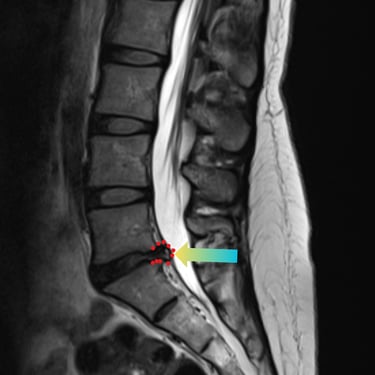

🧠 Fractura Vertebral Lumbar: Estabilización Segura con Fijación Transpedicular (FTP).

La fractura vertebral lumbar genera inestabilidad y dolor severo. La artrodesis con fijación transpedicular es una técnica quirúrgica eficaz que estabiliza la columna, previene desplazamientos vertebrales y mejora la recuperación funcional del paciente.